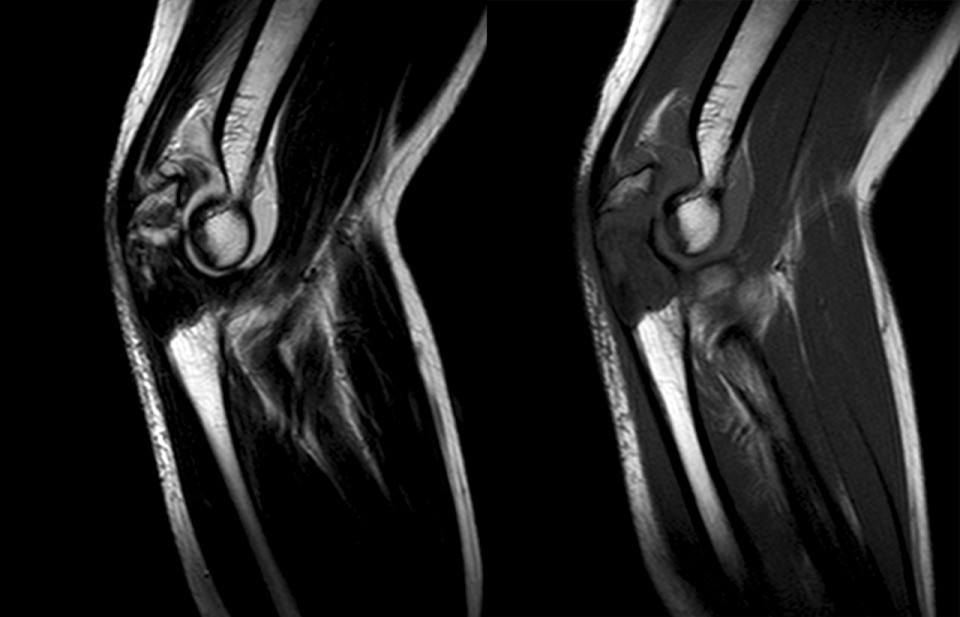

肿瘤对软骨的破坏

肿瘤对骨骺板和关节软骨的破坏是对骨破坏的继续。缺乏血管的骨骺板对恶性肿瘤有抵抗作用,骨骺板可暂时阻止肿瘤的蔓延,但当肿瘤进一步发展时, 骨骺板亦可被破坏,X 线平片或 CT 可表现为先期钙化带密度减低、中断或消失。MRI 可显示肿瘤从干骺端跨越骨骺板侵犯骨骺(图 15、图 16)。肿瘤突破关节软骨向关节腔发展时, 可表现为关节面破坏、塌陷(图 17), 关节腔内出现软组织肿块。少数良性骨肿瘤如软骨母细胞瘤, 亦可超越骺板向两侧发展或突入关节腔内, 此为肿瘤膨胀生长所致, 而非浸润性破坏。

图片

图 15.骨骺板破坏:骨肉瘤

图 16.骨骺板破坏:骨肉瘤

图 17.关节软骨破坏:骨肉瘤